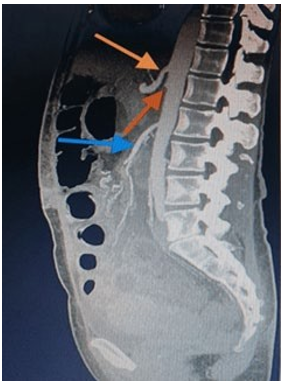

All the included patients had undergone a complete gastroen-terological examination, including upper GI endoscopy, barium contrast series and computed tomography angiography (CTA), to exclude any other cause of duodenal obstruction and to confirm the diagnosis of SMAS. In four patients, in addition to the stud¬ies mentioned above, magnetic resonance angiography (MRA) imaging was used. Ultrasonography (USG) was mainly utilised to exclude biliary pathologies. CTA and MRA enable visuali¬sation of the vascular compression of the duodenum and pre¬cise measurement of aortomesenteric angle and distance . CTA was the most reliable imaging modality to diagnose SMAS, as also mentioned by Lee et al. Early diagnosis is crucial, as delays in diagnosis can result in a chronic course of symptoms, with marked disturbances in fluid and electrolyte balances. The diag- nostic features of imaging modalities included (a) narrowing of the aortomesenteric angle to <25° (Figure (Figure1); (b) short-ening of the distance between the SMA and AA to <8 mm; (c) distension of the stomach and proximal part of the duodenum; (d) and in some cases compression and distention of the LRV.

Figure 1: Arterial phase sagittal view of the aortomesenteric angle of 14 degrees

L1: 1st lumbar vertebra; S: superior mesenteric artery; A: abdominal aorta; Blue arrow:

compressed left renal vein